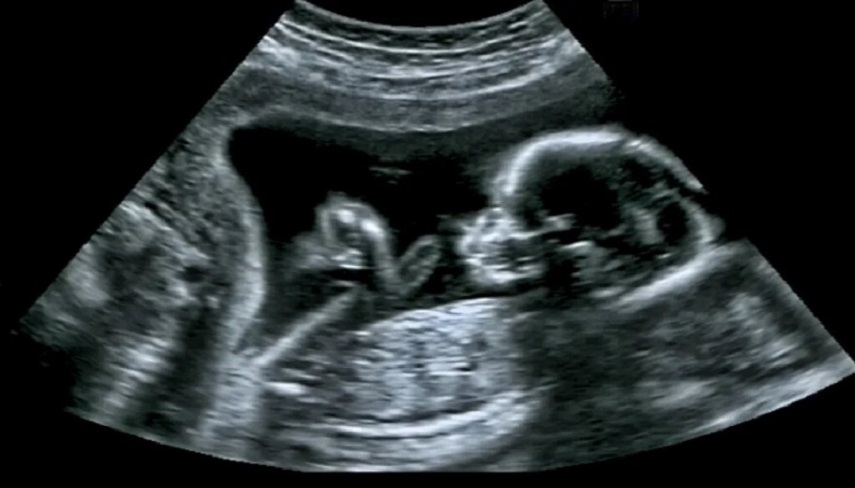

به گزارش پایگاه شبکه الکوثر، این جراحی در بیمارستان امام خمینی(ره) تهران به منظور پیشگیری از خطر سکته مغزی در جنین 34 هفته مبتلا به آنوریسم مغزی (نوعی ناهنجاری عروق مغزی) با موفقیت انجام شد.

دکتر شمشیرساز جراح جنین درباره این جراحی گفت: جنین در 34 هفتگی قرار داشت و دچار عروق ناهنجار مغزی (آنوریسم) شده بود که تحت جراحی قرار گرفت. آنوریسم باعث میشود نوزاد بعد از تولد به دلیل بالابودن جریان خون مغزی در معرض خونریزی و سکته مغزی قرار بگیرد.

استاد دانشگاه علوم پزشکی تهران درباره نحوه انجام این جراحی در دوران بارداری مادر گفت: با استفاده از «آمبولیزاسیون» هدایت شده با سونوگرافی، مسیرهای غیرطبیعی گردش خون در مغز جنین اصلاح شد. در این روش جراحی، یکسوزن از شکم مادر باردار، وارد رحم او میشود و سوزن را تا داخل مغز جنین ادامه میدهیم و به این روش، آنوریسم مغز او جراحی میشود. منظور از آنوریسم مغزی به زبان ساده، تشکیل بادکنکهایی در جداره رگهای مغز است که در بسیاری از موارد منجر به مرگ به دلیل خونریزیهای ناگهانی مغز میشود.

قناعتی با بیان اینکه مادر در هفته سیوچهارم بارداری خود قرار داشت، افزود: هم مادر و هم جنین در شرایط مساعدی قرار دارند.